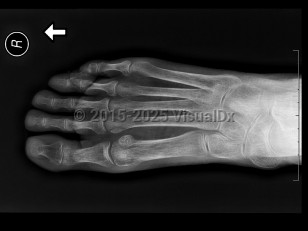

Imaging Studies image of Osteoporosis - imageId=7923513. Click to open in gallery.  caption: '<span>Diffuse osteopenia of the foot  with marked demineralization and decreased cortical thickness of all the bones. These are radiographic findings, which can be seen in the  setting of osteoporosis.</span>'

Diffuse osteopenia of the foot with marked demineralization and decreased cortical thickness of all the bones. These are radiographic findings, which can be seen in the setting of osteoporosis.